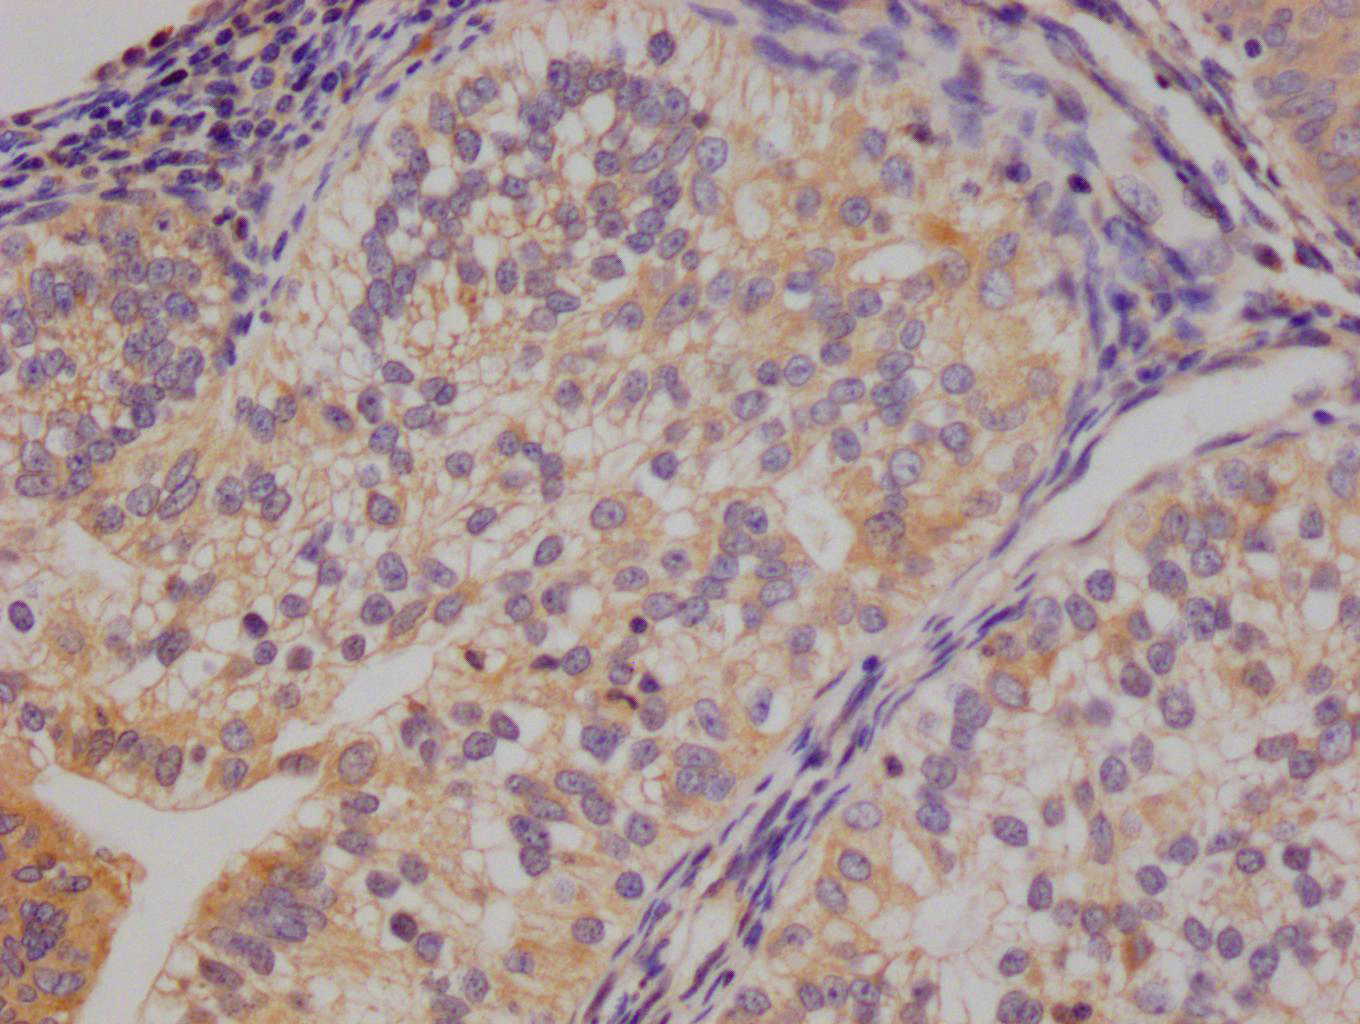

Immunohistochemical analysis of paraffin-embedded Human-testis, antibody was diluted at 1:100

Immunohistochemical analysis of paraffin-embedded Human-testis, antibody was diluted at 1:100